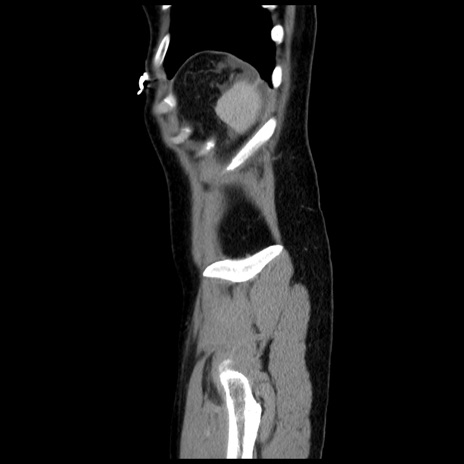

冠状断像